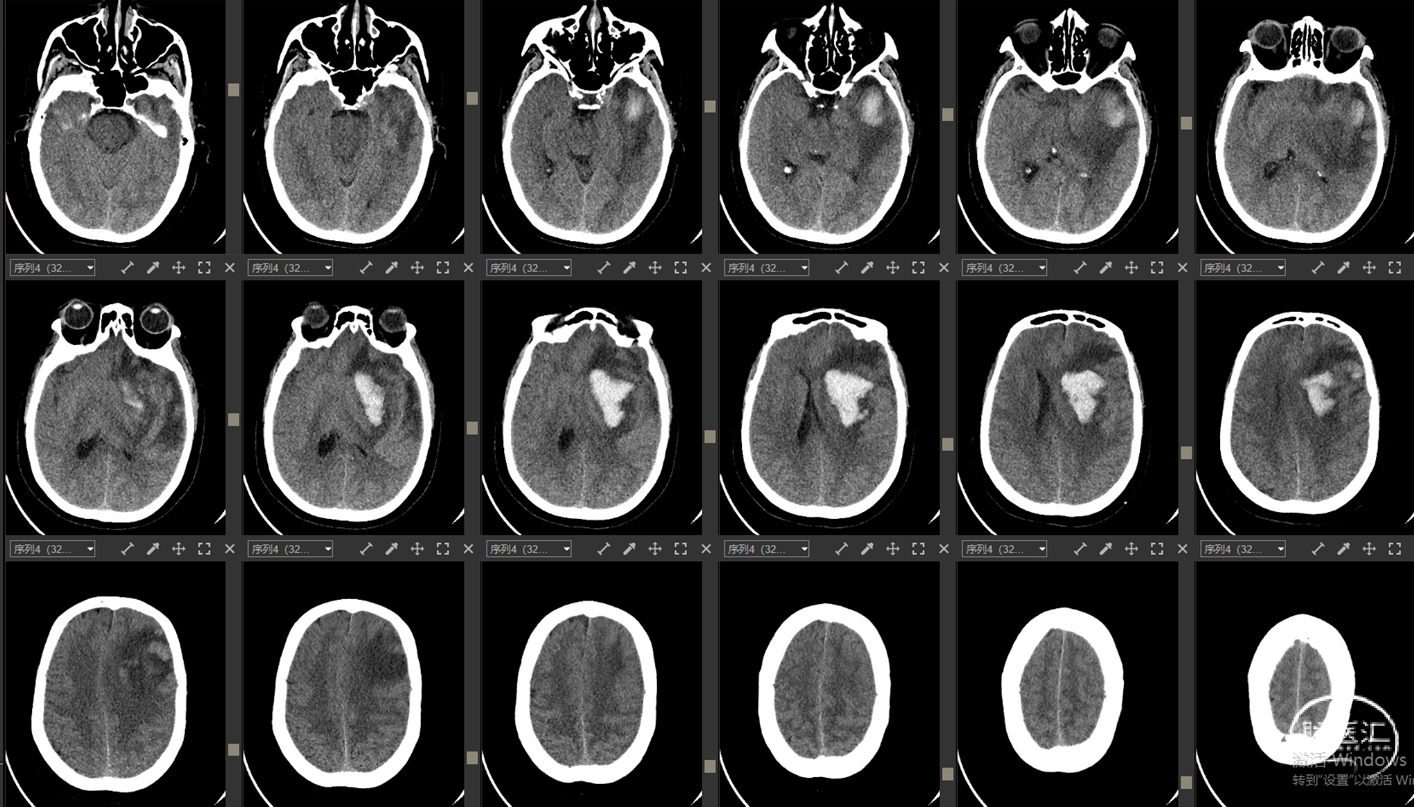

现病史:12小时前无明显诱因突发出现右侧肢体无力,伴言语不能,伴呕吐胃内容物3次,无人事不省,无肢体抽搐,无发热等。就诊当地医院,急查头颅CT示:“颅内出血”,予对症处理后转诊我院。我院急诊查头颅CTA示:“左侧基底节区及左侧额颞叶血肿伴大脑镰下疝、颞叶钩回疝及海马旁回疝可能,左侧颈内动脉C4段所见,考虑多发动脉瘤伴血管畸形,建议DSA检查”。

影像资料:CT、CTA

1.左侧基底节区及左侧额颞叶血肿 2.左侧颈内动脉C4段多发动脉瘤 3.左侧额颞叶血管动静脉畸形

1. 左侧基底节区及左侧额颞叶血肿

2. 左侧颈内动脉C4段动脉瘤破裂致颈内动脉海绵窦瘘

3. 左侧额颞叶血管动静脉畸形?

1. 左侧基底节区及左侧额颞叶血肿

2. 左侧颈内C4段动脉瘤破裂致颈内动脉海绵窦瘘(Barrow A型)

精确诊断:左侧颈内C4段动脉瘤破裂至大脑中浅静脉致左侧基底节区及左侧额颞叶静脉性梗死并出血转化。